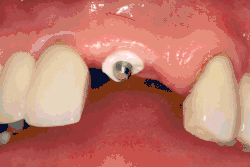

Single tooth implant restoration

Single tooth restorations are individual freestanding units not connected to other teeth or implants, used to replace missing individual teeth.[23] For individual tooth replacement, an implant abutment is first secured to the implant with an abutment screw. A crown (the dental prosthesis) is then connected to the abutment with dental cement, a small screw, or fused with the abutment as one piece during fabrication.[28]: 211–232 Dental implants, in the same way, can also be used to retain a multiple tooth dental prosthesis either in the form of a fixed bridge or removable dentures.